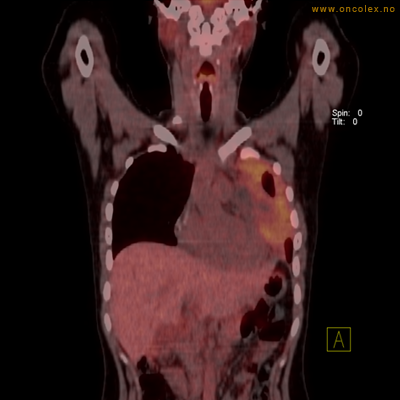

Vev som tar opp mer radioaktivt stoff, synes som hvite områder som lyser opp mer i forhold til annet vev som tar opp mindre sukker.

Moderat opptak i bløtvevssarkom venstre halvdel av brystkassen. Områder med lavere opptak antas å skyldes dels betennelse som skyldes svulsten, dels svulstnekrose.

Moderat opptak av FDG i bløtvevssarkom venstre halvdel av brystkassen. Områder med lavere opptak antas å skyldes dels betennelse som skyldes svulst, dels svulstnekrose.